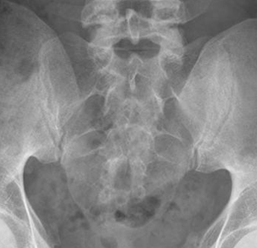

En la radiología simple, la proyección de Ferguson es de elección para la valoración de las SI. Consiste en una proyección AP, con angulación cefálica del rayo de 30º. (1). (Fig 3).

Fig 3. Proyección de Ferguson normal.